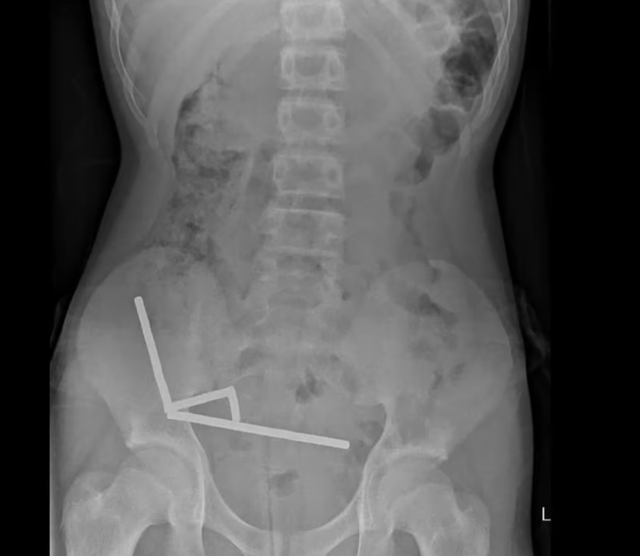

Khai tác tiền sử bệnh trước khi được đưa đến bệnh viện, cậu bé đã chịu đựng cơn đau bụng kéo dài bốn ngày. Tại đây, em cho biết đã nuốt số nam châm này khoảng một tuần trước đó. Kết quả chụp chiếu cho thấy chúng đã kết lại thành bốn chuỗi trong ổ bụng, kéo các đoạn ruột lại với nhau bằng lực từ. Hình ảnh bị nhiễu do từ tính mạnh buộc các bác sĩ phải tiến hành phẫu thuật khẩn cấp.